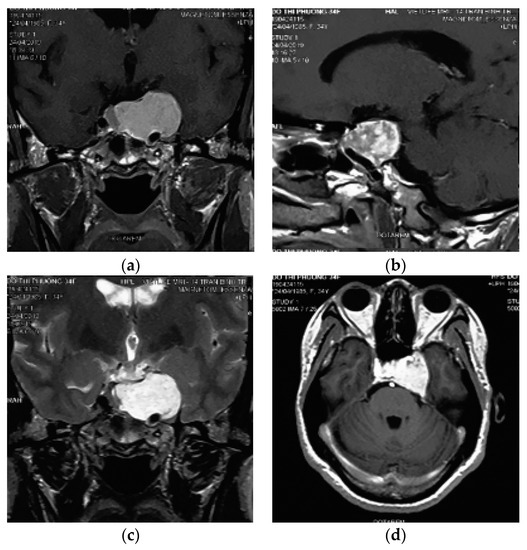

After incising the inner layer of the lateral wall of the cavernous sinus, along the path of the V2 branch nerve and partial resection this nerve, the tumor inside the sinus was exposed as a soft porous mass that was easy to bleed but it could be stopped by squeezing or spongel. The tumor could be completely dissected, and separated from the carotid artery and the sinus cavity with a blunt tool to avoid damaging the blood vessels in the sinus. Some authors suggested that CSC should be removed in bloc dissection [8,11,24]; however, this method is only suitable for small and medium tumors. For large tumors, they should be taken in small pieces (debulking dissection) to stop bleeding with pressed cotton, which will reduce blood loss and bleeding during surgery. In the places where veins flow into the cavernous sinus, after tumor resection, we used a spongel inserted into it to stop the bleeding. With the bleeding from the artery feeders, mini clips were used, and electronical coagulation was limitted due to ICA constriction. We observed that this method of hemostasis was very effective, which ensured that the surgical field was not flooded by blood, helping the dissection and resection process to be increasingly more safe and reducing blood loss. During the operation, the sinus cavity was opened in a straight line, parallel to the V2 nerve; hence, as the dissection on the arch of the sinus cavity, we had to lift the lateral wall of the cavernous sinus upward. This manipulation might have damaged the thrid nerve, leading to thrid nerve paralysis postoperatively. However, this condition was temporary, as the third nerve was almost fully recovered after acupuncture for 3 months. The phenomenon of maxillary facial numbness (corresponding to the V2 branch) has been predicted intra surgery. Postoperative magnetic resonance imaging showed that the tumor was mostly removed (Figure 4).

Figure 4.

Three-month postoperative magnetic resonance imaging.